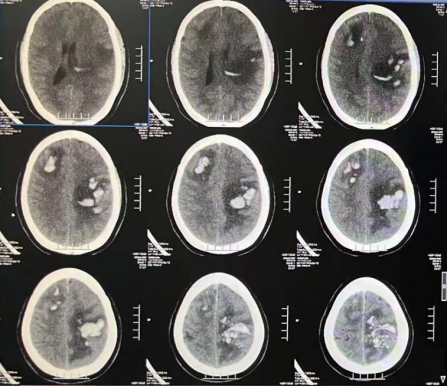

“患者入院时意识昏迷,情况危急,立即转入了重症医学科。”该院神经外十科欧阳辉教授介绍,患者是年轻产妇,颅内多发出血且形态不规则,并非是常见的脑出血,而是大静脉窦血栓导致脑静脉血液回流受阻,压力增高引起的淤积性出血。

影像提示:颅内多发出血且形态不规则

神经外十科及神经血管介入科急诊为患者行全脑血管造影。结果显示患者的上矢状窦、右侧横窦等颅内大静脉完全堵塞,证实是大静脉窦血栓。欧阳辉教授表示,虽然出血十分严重,但不能轻易开颅清除血块,应先对因治疗,疏通大血管(静脉窦)。否则患者的病情会持续恶化,危及生命。